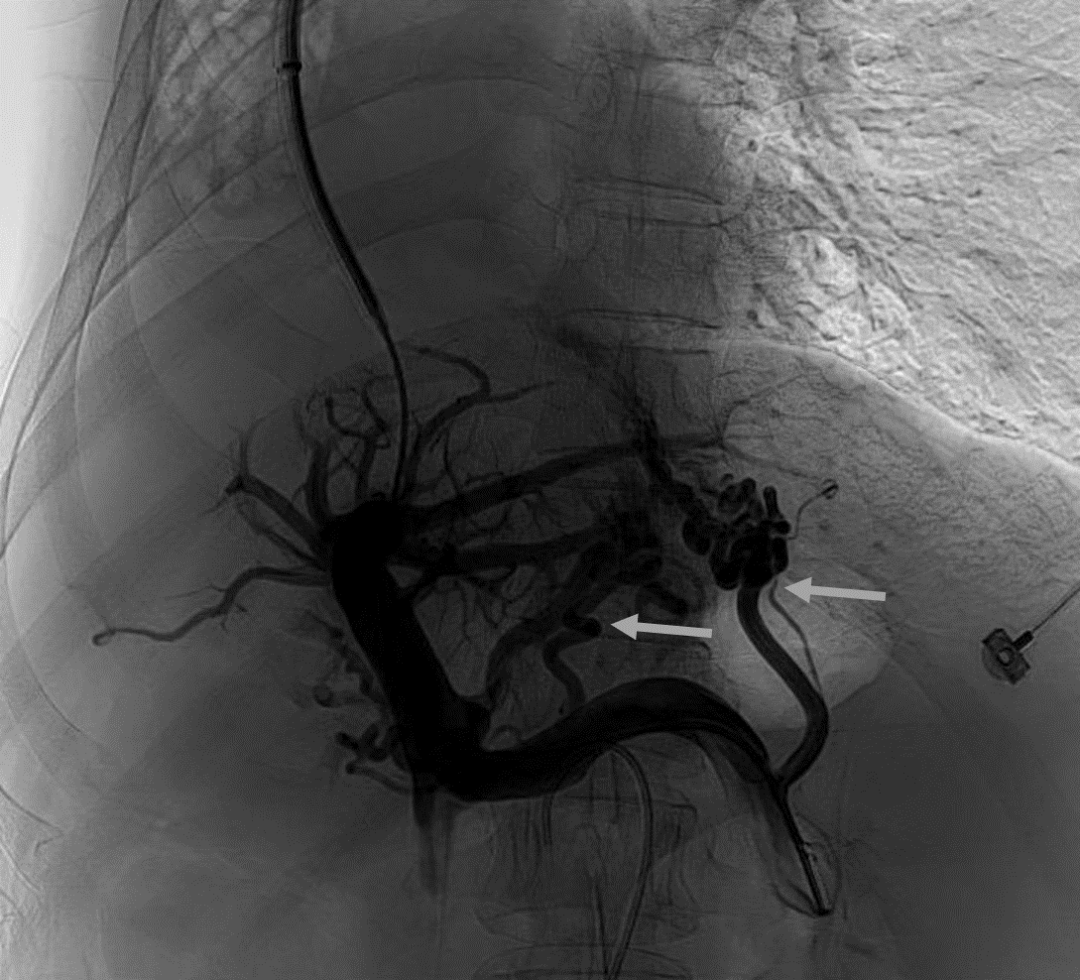

韓國宏教授介紹,TIPS手術(shù)是通過在肝靜脈與門靜脈之間的肝實質(zhì)內(nèi)建立分流通道,通過降低門靜脈壓力來預防和治療因門靜脈高壓引起的食管胃底曲張靜脈破裂出血或頑固性腹水。該手術(shù)不用開刀、創(chuàng)傷小、操作過程復雜、技術(shù)難度大、安全風險高,是目前外周血管介入中難度最大的手術(shù)之一。再加上人群中右位心發(fā)病率極低(約萬分之一),經(jīng)查閱文獻,在國內(nèi)外尚未有類似病例報道,無經(jīng)驗參考。在右位心基礎(chǔ)上行TIPS術(shù),無疑是難上加難。我們反復研究患者肝臟及心血管的特殊情況,詳細討論了手術(shù)方案,決定放棄常規(guī)的肝靜脈穿刺,另辟蹊徑,選擇高難度高風險的肝后段下腔靜脈穿刺門靜脈左支,憑借多年的經(jīng)驗和嫻熟的技術(shù)最終成功的在下腔靜脈與門靜脈之間放置了TIPS專用支架,術(shù)后門靜脈壓力梯度從術(shù)前的19mmHg降至3mmHg,曲張靜脈消失,解決了困擾曹女士多年上消化道出血的困擾?;颊咝g(shù)后第二天即可正常下床活動。